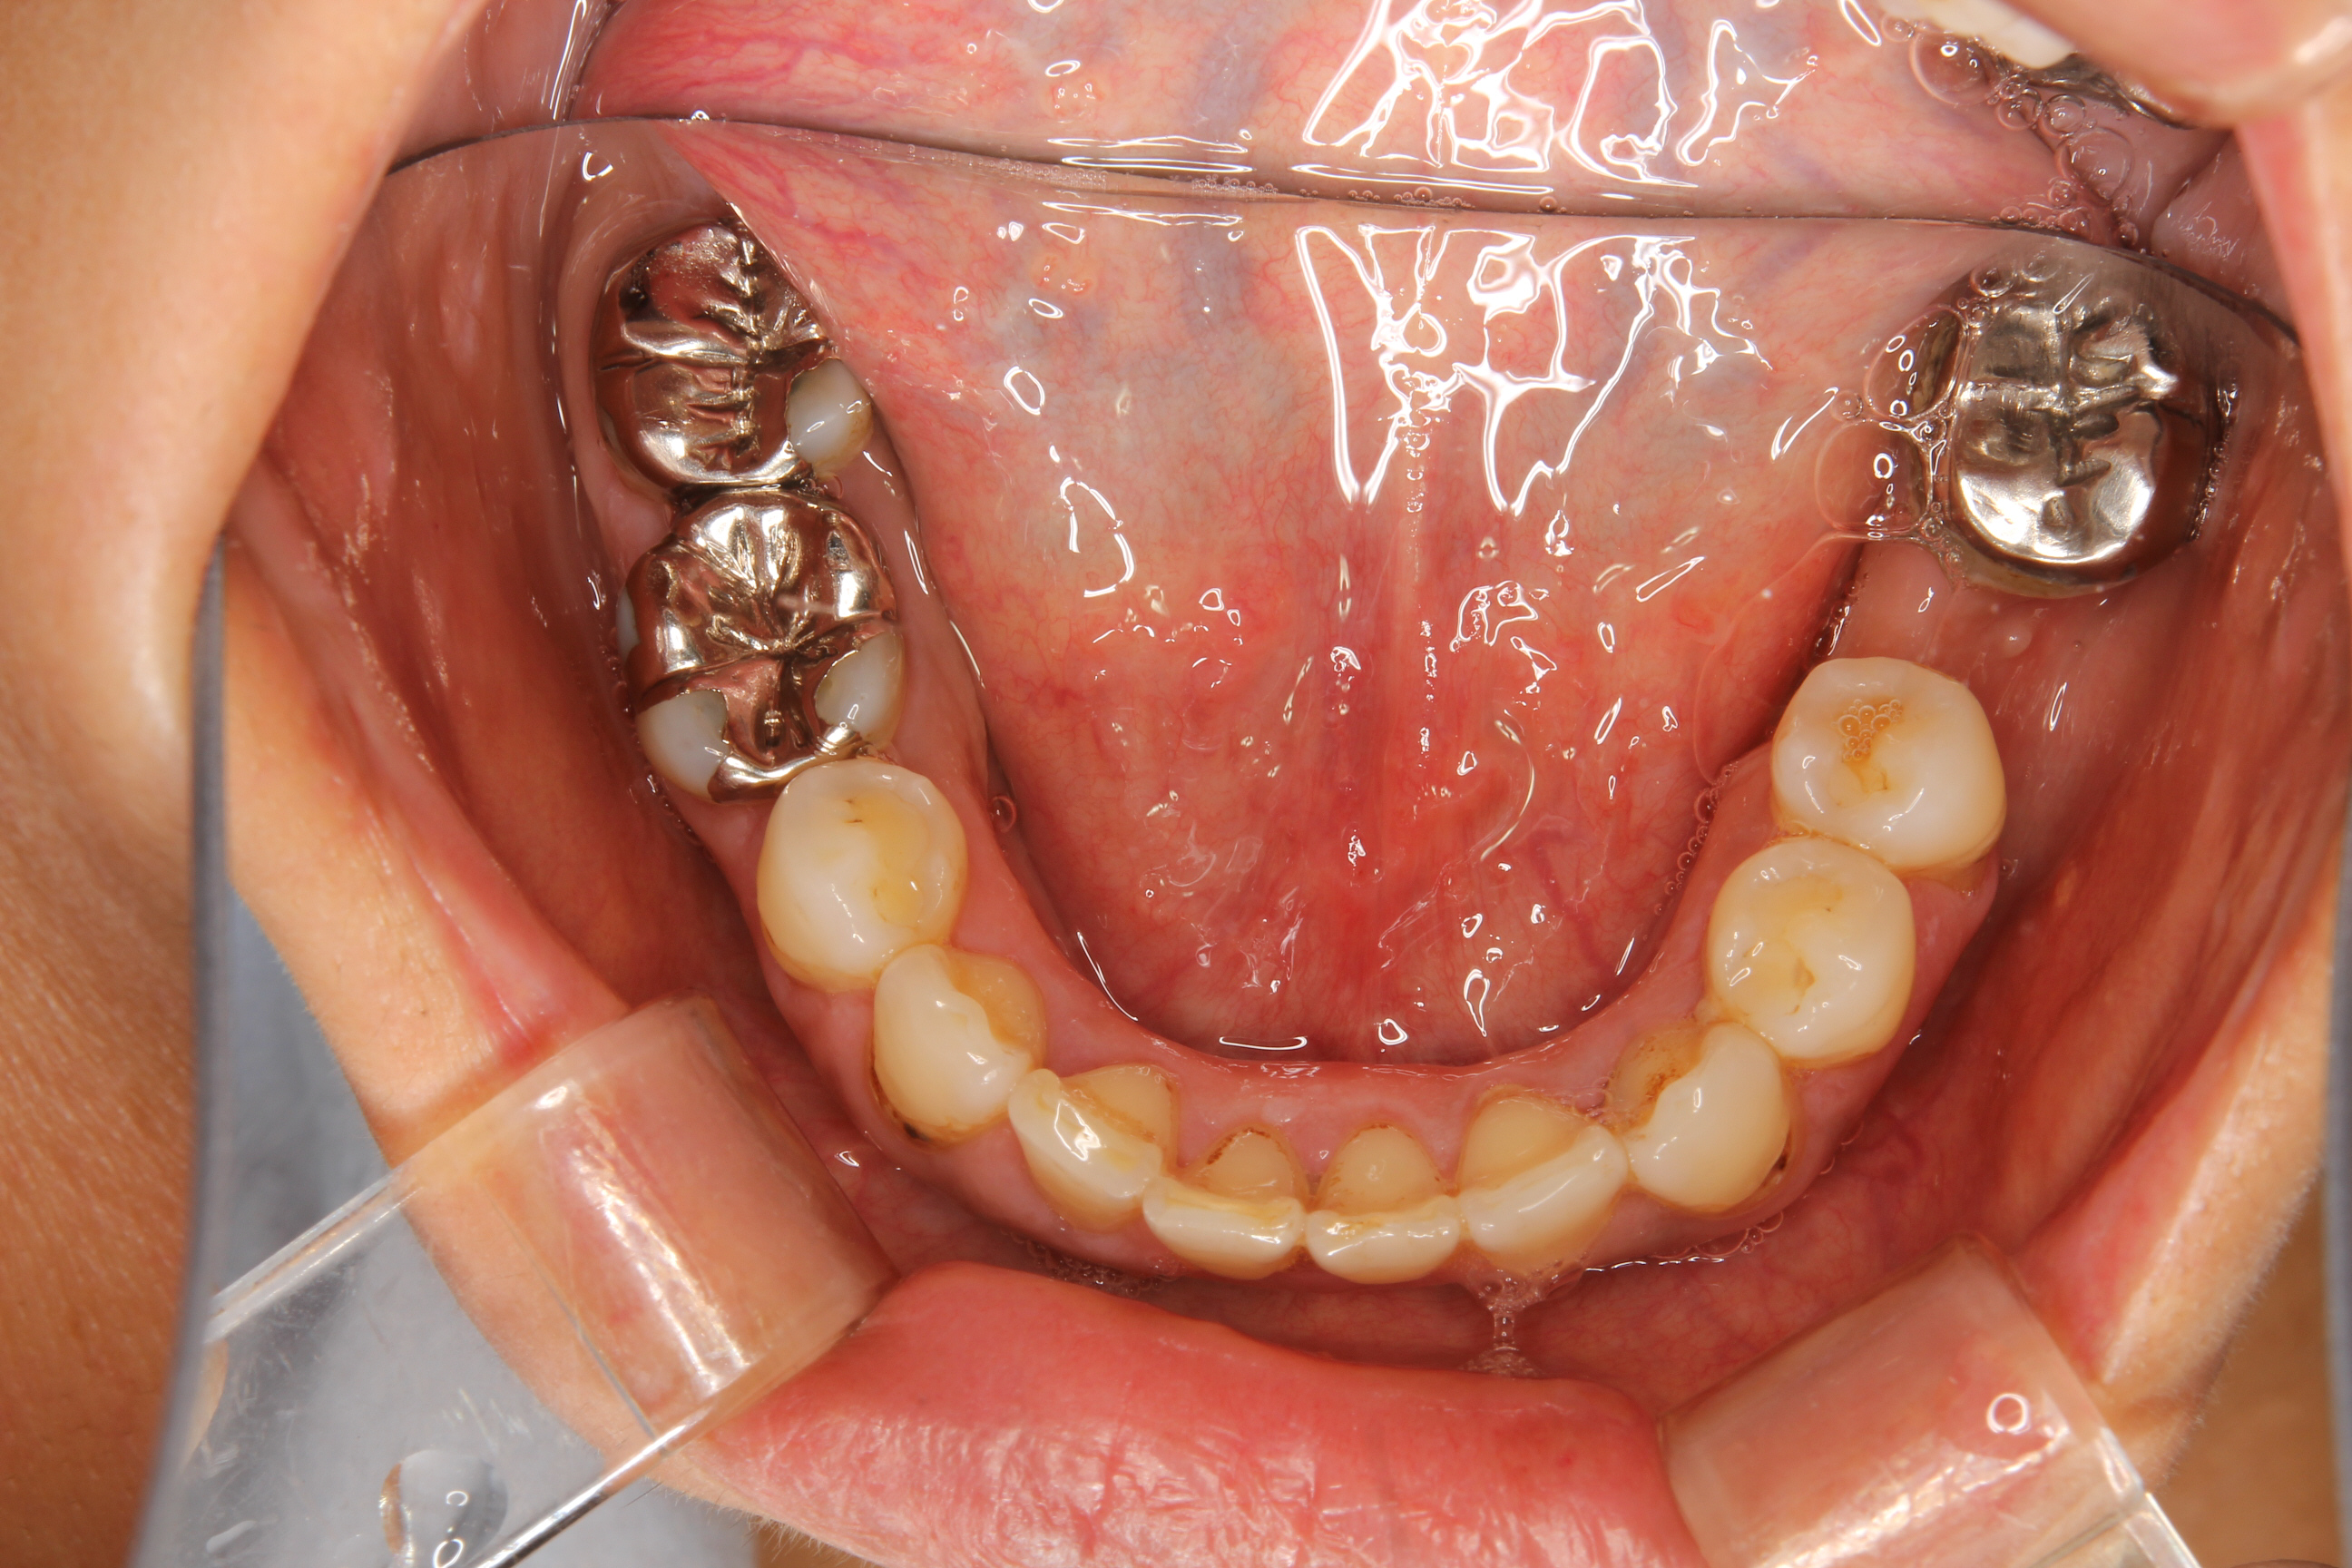

口腔内を見ると、全体的にむし歯があり、一部の歯には根の病気(根尖病巣)も認められました。

歯科金属のアレルギー検査なども行い、その結果に基づき、口腔内からすべて歯科金属を除去し、アレルギーを惹起しない材料を用いてメタルフリーの修復を行いました。

すべての治療が終わり、メインテナンス時の状態がこちらです。

むし歯や根尖病巣も改善され、口腔内からすべてのメタルが無くなり、歯も歯肉も見た目も良好になりました。